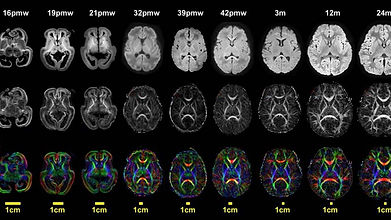

The ultimate product of our Center will be a series of comprehensive developing human and non-human primate (NHP) brain atlases of unprecedented cellular, spatial, and anatomical resolution. In Aim 1, we will characterize transient cell populations, establish the diversity of cell types present in specific brain regions, unravel complex developmental trajectories, and reveal conserved and divergent cell-type specific features. We will jointly profile of single nucleus RNA (snRNA-seq) and accessible chromatin (snATAC-seq) using the 10X Genomics snMultiome platform. All aims will include 30 anatomically distinct regions of fresh frozen developing human, rhesus macaque, and marmoset brains at four developmental epochs: mid-gestation, neonatal, childhood, and adolescence and perform probe-based validation. In Aim 2, we will conduct spatial transcriptomic and epigenomic mapping of cell types in fresh-frozen developing human and NHP brains using DBiT spatial-RNA-seq and spatial-ATAC-seq platforms. This approach will allow us to discover spatial and temporal features, including the developmental niche, proximity of cell types to each other, and regional abundance. In Aim 3 we will create Common Coordinate Frameworks for the developing human and NHP brain using high resolution (9.4T and 7T) MRI-based developmental structural atlases and leveraging existing developing human MRI data. Our final aim will create a cross species molecular and spatial atlas of brain development in human and NHP. This integration will enable us to identify conserved and diveregent aspects of the human brain and identify the developmental stages, spatial distribution, gene regulatory elements and cell types vulnerable to neurodevelopmental and neuropsychiatric disorders. We will coordinate to ensure that our developmental atlases merge with adult human, macaque and marmoset atlases that other BICAN centers create. The data collected by our Center will be perfectly aligned with the overarching goal of the BICCN in generating a comprehensive census of brain cell types across the lifespan that integrates molecular, anatomical, functional, and cell lineage data for describing cell types in human and NHP brains. By leveraging innovations in cell capture and spatial mapping technologies, the current proposal will have broad implications for understanding the cellular origins of diseases and for highlighting patterns of selective cell type vulnerability in neurodevelopmental disorders such as autism and schizophrenia. Additionally, our plans to create developmental cellular and molecular resolution maps of marmoset and macaque will provide foundational data for establishing primate models of human disease. Finally, our atlas of conserved molecular, epigenetic, and spatial properties will support the precise monitoring, targeting, and replacement of specific cell types and the improvement of in vitro models.